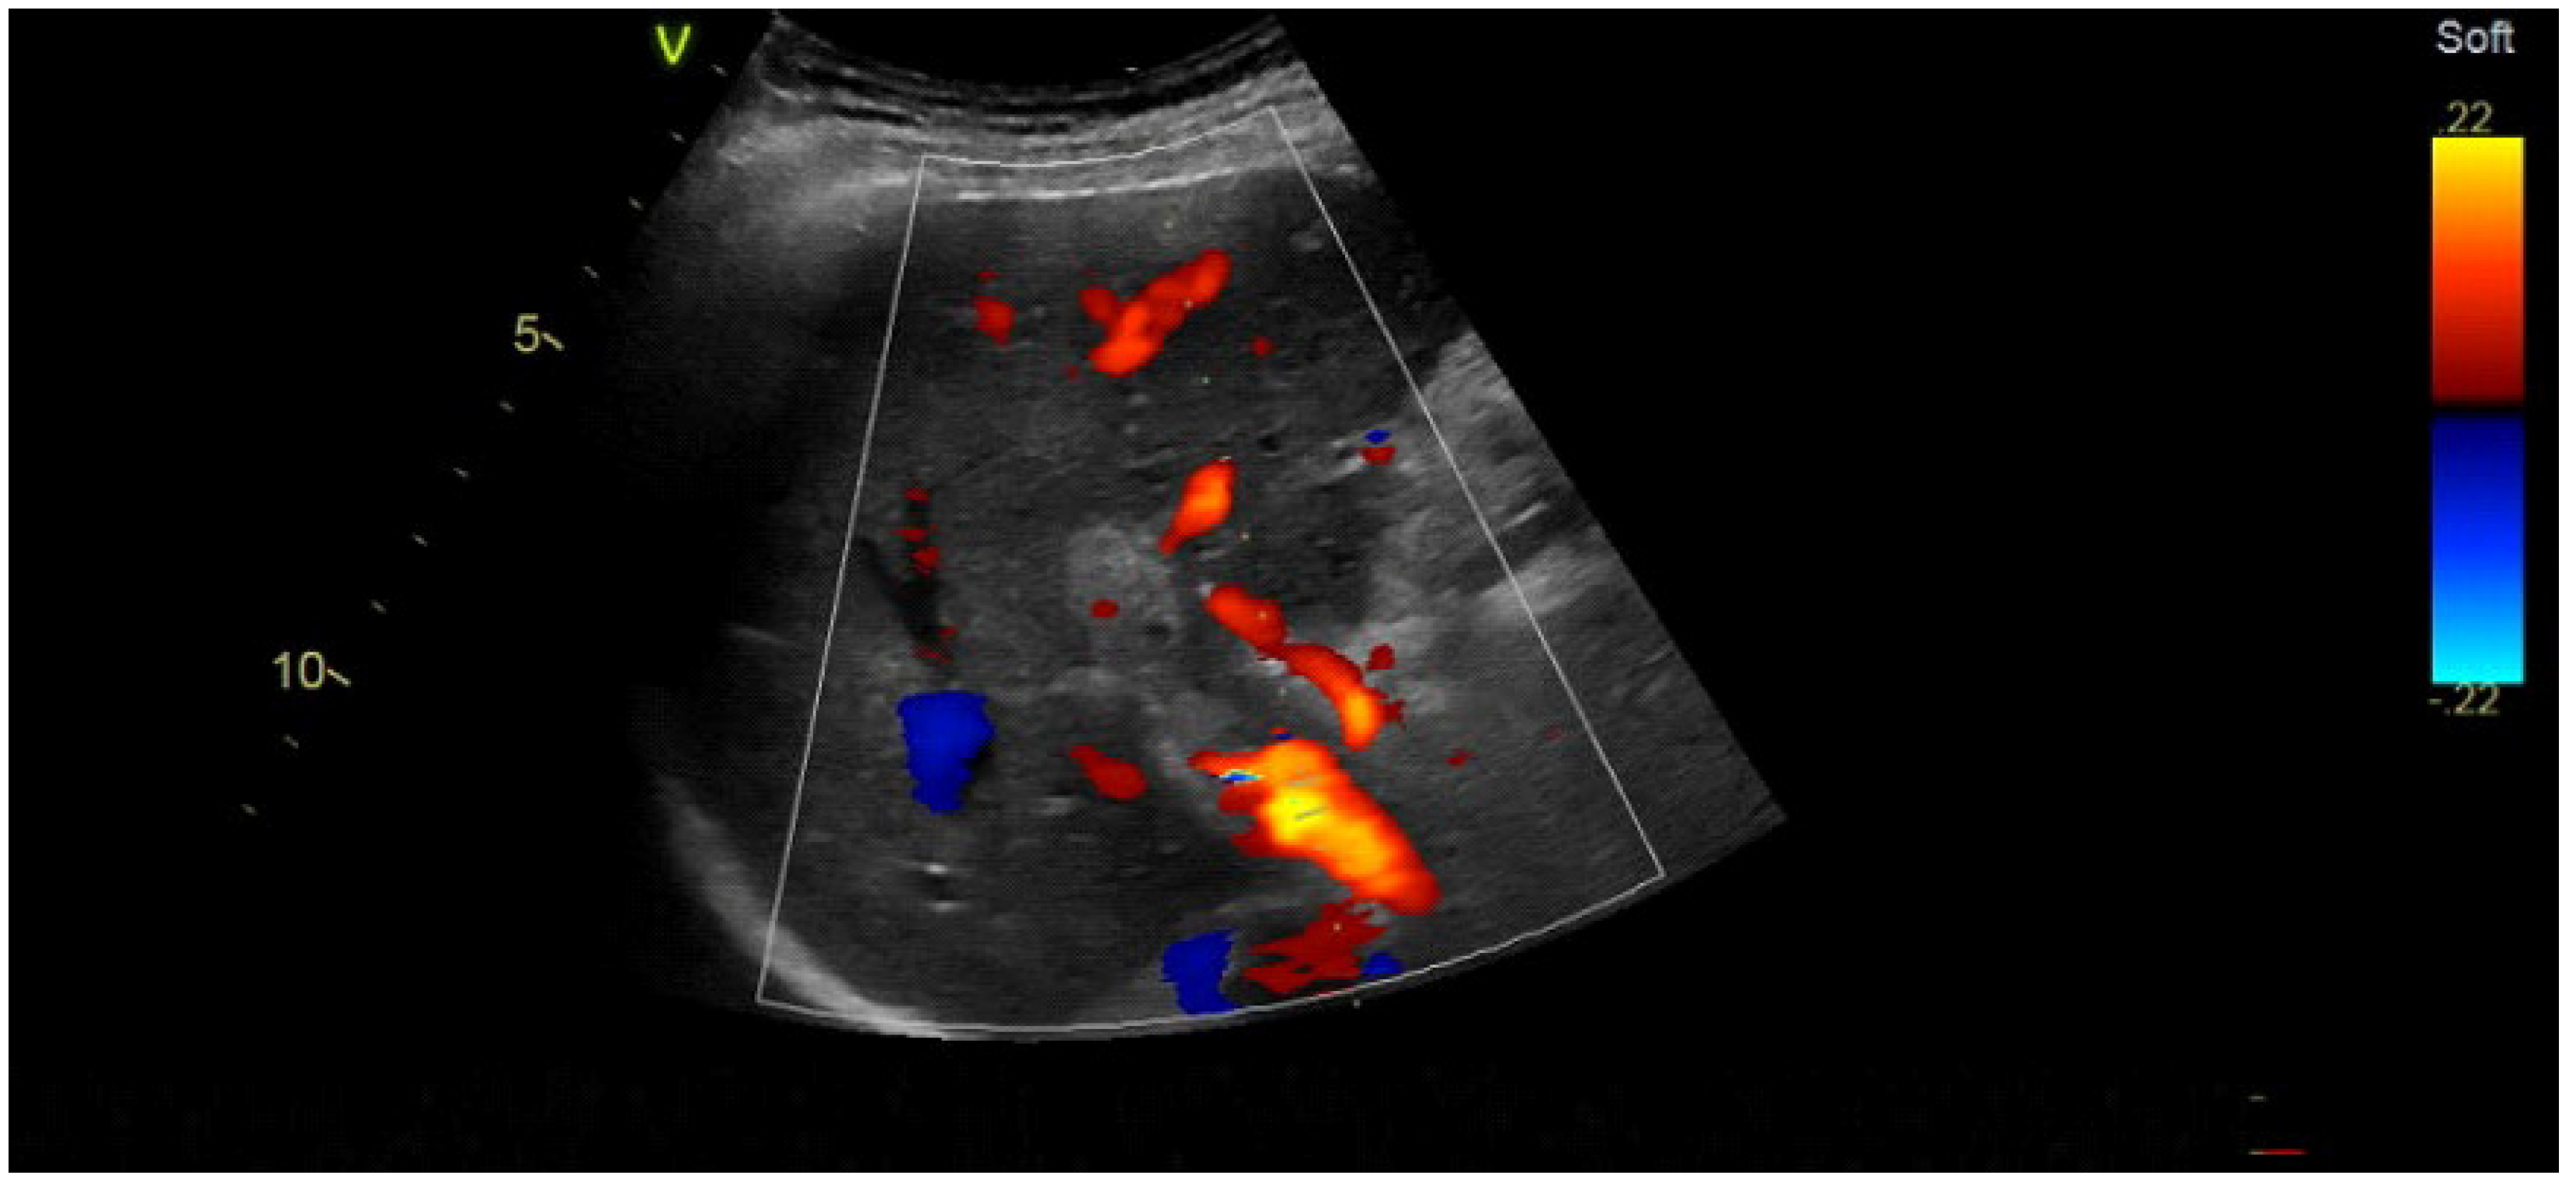

2.2. Imaging Methods